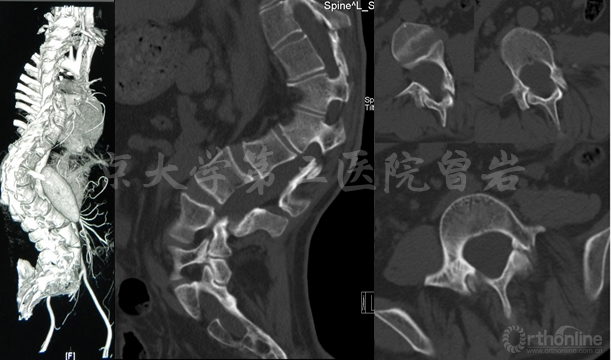

CT(图7):显示脊柱侧后凸畸形,腰骶段椎管扩大,椎体扇贝样改变,椎弓根发育异常,L5峡部不连。

图7